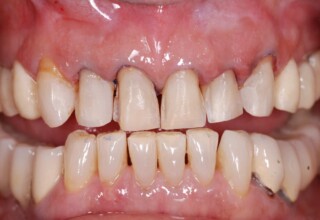

Εκτεταμένο Περιστατικό Ακίνητης Αποκατάστασης

Εκτεταμένη αποκατάσταση με στεφάνες(θήκες) σχεδόν σε όλα τα δόντια λόγω εκτεταμένων αποτριβών, παλαιών αποκαταστάσεων, οπισθίων απονευρώσεων και αισθητικών προβλημάτων. Ο ασθενής(60 ετών) παρουσίαζε έντονο βρυγμό (τρίξιμο δοντιών) που δεν είχε αντιμετωπίσει ποτέ, με αποτέλεσμα μεγάλες αποτριβές που απειλούσαν την ακεραιότητα των οπισθίων δοντιών. Οι ανασυστάσεις(σφραγίσματα) των δοντιών έγιναν κυρίως με συγκολλούμενα ρητινώδη υλικά και τρεις χυτούς άξονες ψευδοκολοβώματα. Τοποθετήθηκαν προσωρινές στεφάνες όπου εκτιμήθηκε το επιθυμητό μέγεθος, το σχήμα και η θέση των δοντιών πριν κατασκευαστούν οι τελικές μόνιμες στεφάνες.

Αρχικό χαμόγελο

Τελικό χαμόγελο